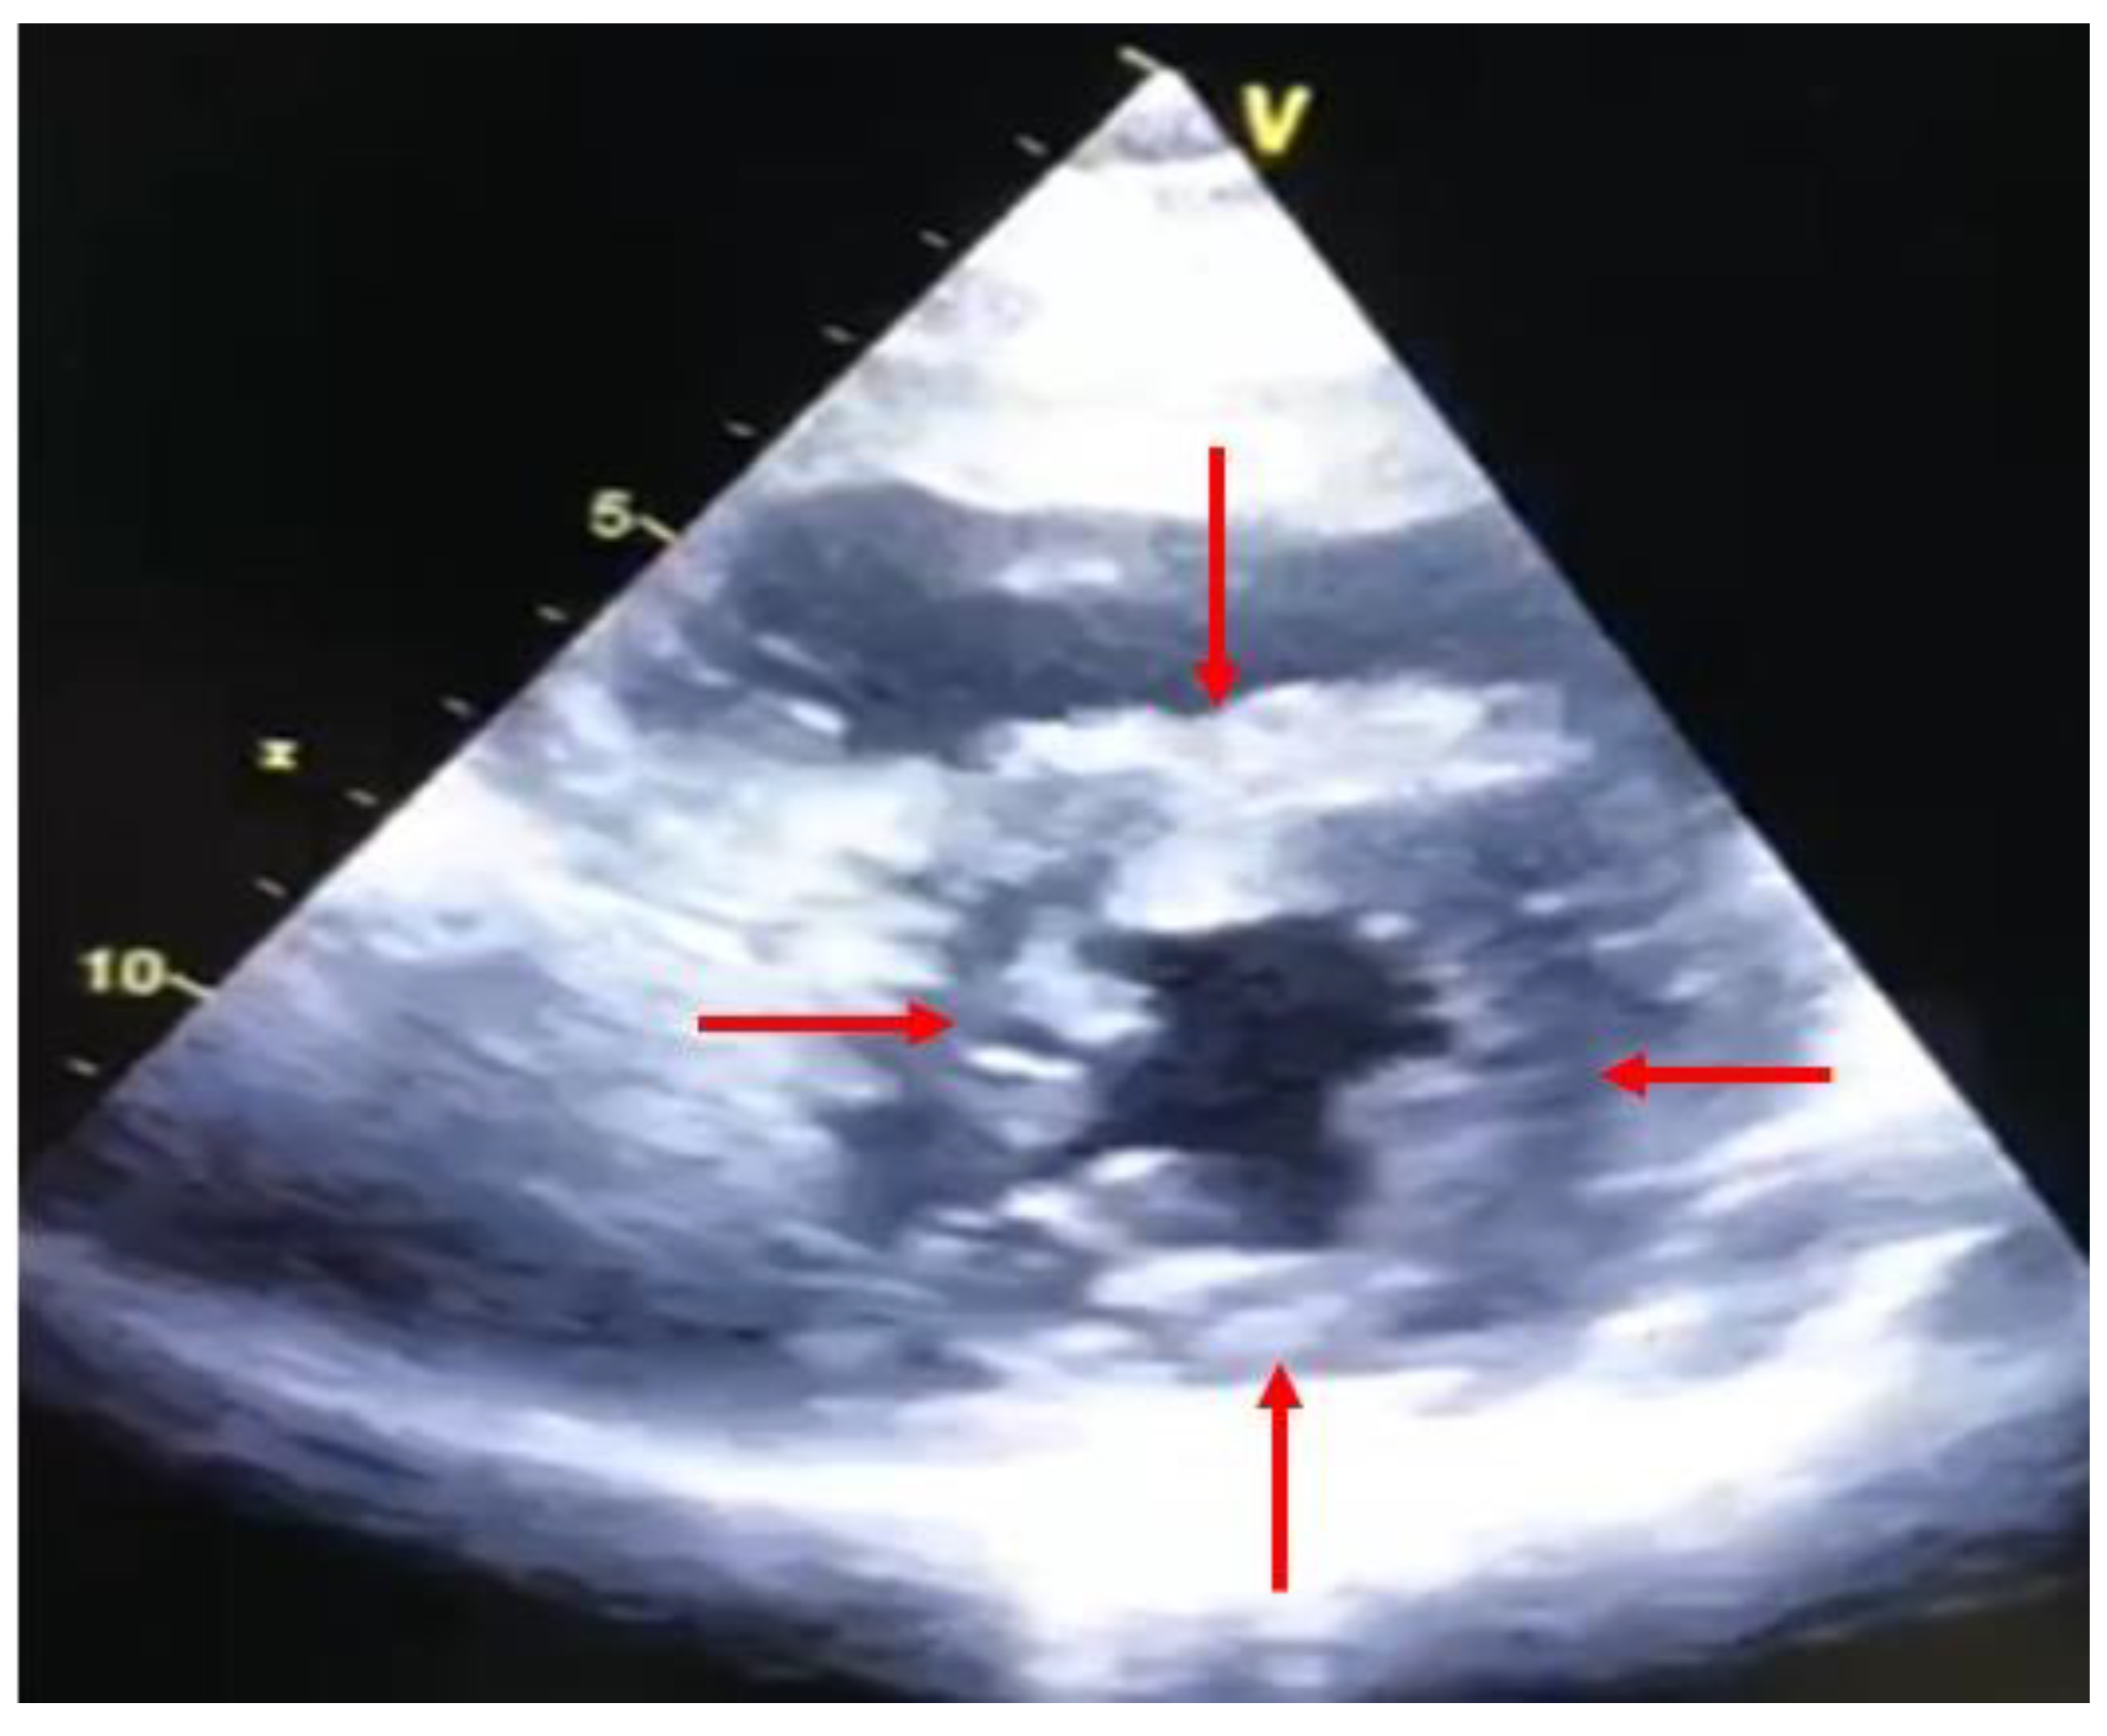

3. Role of Echocardiography in the Evaluation of Primary Graft Dysfunction

4. Role of Echocardiography in the Evaluation of Acute Graft Rejection